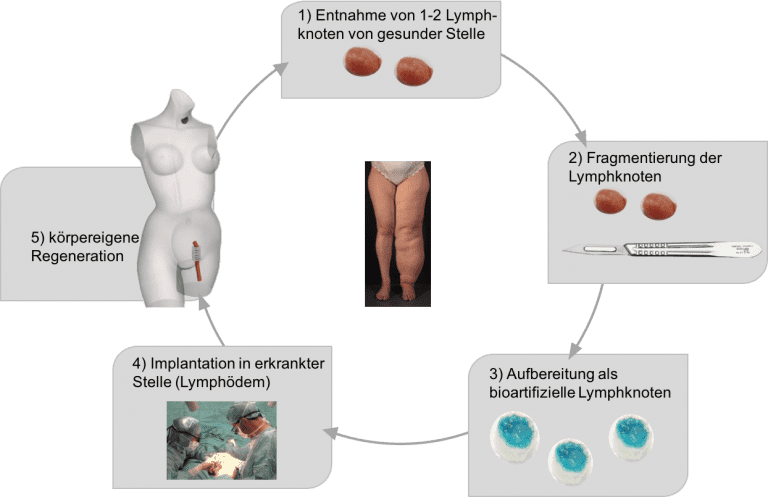

Das chronische Lymphödem ist eine Erkrankung des Lymphgefäßsystems, bei der es zu einer Ansammlung von Lymphflüssigkeit im Gewebe kommt. Die entsprechende Region schwillt an und die Patienten sind kosmetisch aber auch funktionell stark eingeschränkt. Der Goldstandard weltweit ist weiterhin die konservative Therapie (komplexe physikalische Entstauungstherapie). Zu den derzeit bedeutendsten chirurgischen Therapieformen zählt die mikrochirurgische Lymphknotentransplantation, die vor allem in den letzten 10 Jahren zunehmend an Popularität gewinnt. Dabei wird von der gesunden Seite ein Lymphknotenpaket entnommen und dieses mikrochirurgisch in der erkrankten Region an ein Empfängergefäß angeschlossen. Ein wesentlicher Nachteil dieser Technik ist jedoch die lange OP-Zeit von bis zu 5 Stunden und das Risiko ein neues Lymphödem an der Entnahmestelle zu verursachen.

Unser Forschungsziel ist es ein neues innovatives Verfahren zu etablieren, die sog. Bioartifiziellen Lymphknoten. Dabei werden gezielt nur 1 oder 2 Lymphknoten entnommen, mechanisch zerkleinert und auf PCL Scaffolds mit biologischem Gel fixiert. Diese werden dann in derselben Sitzung in die erkrankte Region transplantiert ohne Mikrochirurgie. Die Lymphknoten regenerieren und es kommt zur einer Neubildung von Lymphgefäßen.

Durch diese Technik verkürzt sich die OP-Zeit wesentlich und das Risiko ein neues Lymphödem auf der gesunden Seite zu verursachen wird deutlich verringert. Erste Tierversuche in Mäusen und Minischweinen zeigen bereits das hohe Regenerationspotenzial von Lymphknotengewebe und erste Hinweise für Lymphgefäßneubildung.